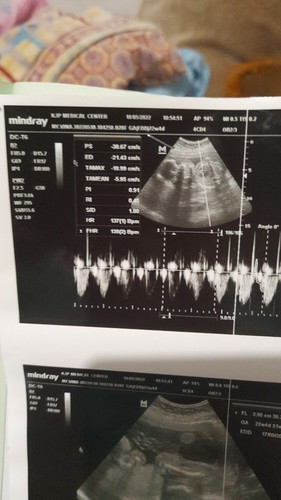

Assalamualaikum bunda" , mau cerita dan mau bertanya juga . Tadi subuh saya mengalami perut keram bagian bawah bisa di bilang seperti kontraksi palsu dan itu sangat sakit , durasi sakitnya dari jam 5 sampai stgh 7an bun . Tapi Alhamdulillah tidak keluar flek sama sekali . Lalu jam 10an saya usg , dan bidan bilang kalau bayi dan ari ari nya berada di bawah , tapi tidak menutup jalan lahir , karena itu terjadi kontraksi palsu tadi pagi bun . Dan saya tanya ke bidan nya semua sehat semua normal hanya saja posisi bayi dan ari ari nya berada di bawah . Dan menurut bidan yg lain itu di namakan plasenta previa dan harus di observasi lagi ke dokter kandungan di RS . Apakah ini berbahaya bund ? Usia kandungan saya 22weeks. Ada yg punya pengalaman sama seperti saya ? Bidan menyarankan untuk bedrest total , kurangi aktivitas berat dan kurangi berkendara motor , karena aktivitas sehari hari saya kebanyakan mengendarai motor bun . Dan saya kerja sebagai mua , yg posisi nya harus berdiri beberapa jam dan gabisa makeup client dengan posisi duduk . Bidan jelasin katanya aman selama tidak mengeluarkan flek . Ini hasil usg saya.

G5P2A2